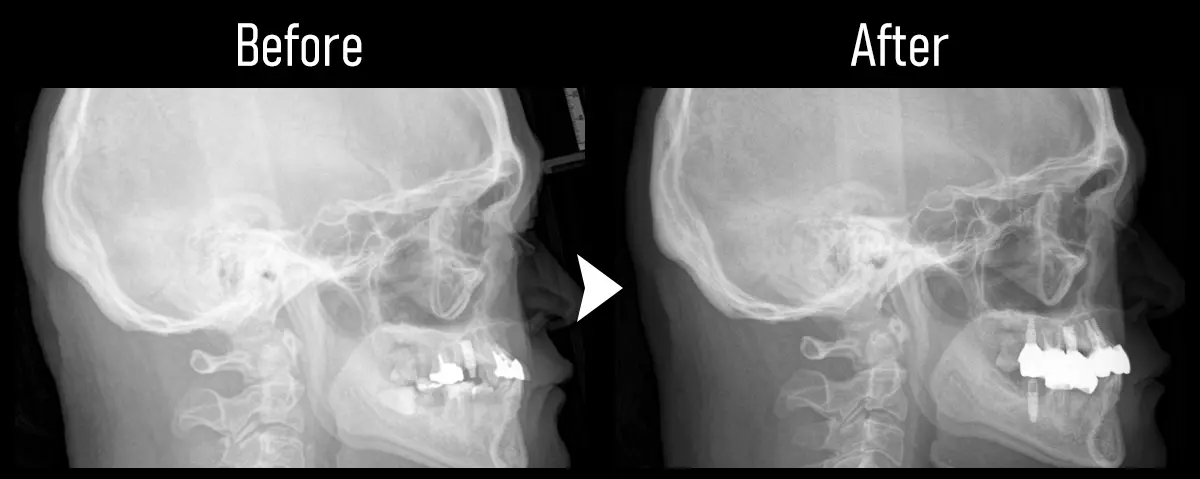

CASE:下顎のAll-on-4(オール・オン・フォー)

主訴 全体的に歯がグラグラしていて噛めない

治療内容 下顎をAll-on-4(オール・オン・フォー)で治療

標準費用(自費) 330万円